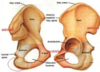

delineate the general areas of the: ___ ilium ___ ischium ___ pubis

___ ant sup iliac spine (ASIS) ___ ant inf iliac spine (AIIS) ___ posterior superior iliac spine (PSIS)

___ pubic tubercle & crest ___ obturator foramen ___ auricular /articular surface of SI joint

___ iliac tuberosity

___ iliac fossa ___ pubic symphysis

___ ischial tuberosity ___ greater sciatic notch

___ lesser sciatic notch ___ ischial spine ___ acetabulum